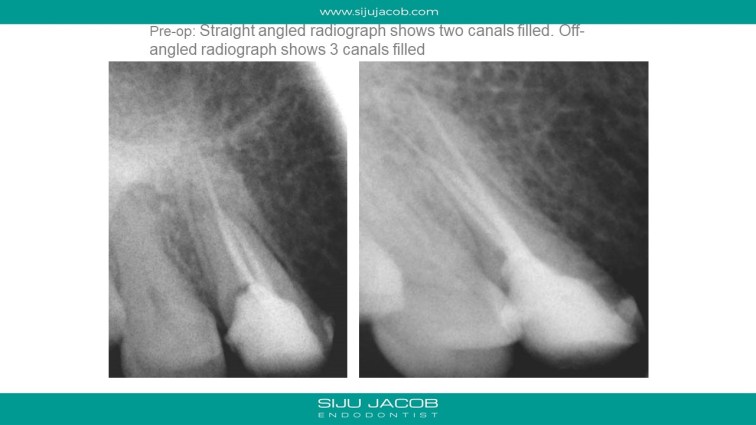

And here are the slides for the cases: